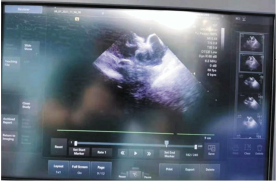

患者术中房颤转为规整房扑心律

术中患者房扑转为正常心跳

此次病例患者郭某,男,61岁,因“间断胸闷、气短1月余,加重1周”之主诉入院,既往有心房颤动2年。王洪涛教授接诊患者后,综合评估患者的病情,因患者CHADS2评分大于2分,属血栓高危人群,因此建议患者行房颤射频消融+左心耳封堵一站式手术。王洪涛教授采用OCE方案,首先应用STSF导管进行高效消融,提高消融效率及安全性,更少的盐水灌注使房颤合并心衰患者亦能平安完成消融。接着采用辅助vizigo可视化可调弯鞘增加导管到位几率并大幅降低X曝光,几乎实现零射线全程消融。最后用心腔内超声(ICE)指导进行实现精准的左心耳封堵手术。该方案为房颤射频消融的新技术、新理念。